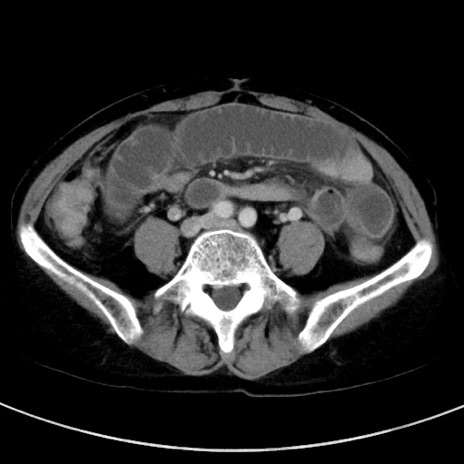

症例23(横断像)

【症例】70歳代女性

【主訴】下腹部痛・嘔吐

【現病歴】2日前より腹痛あり。昨日嘔吐あり。症状改善しないため来院。

【既往歴】胃GISTに対して胃部分切除後。

【身体所見】BT 37.1℃、BP 128/77mmHg、腹部:平坦・軟、下腹部に圧痛あり。

【データ】WBC 10200、CRP 0.31